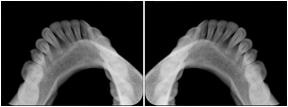

2. A patient requests cosmetic surgery to enhance their facial appearance. The case requires consultation between an orthodontist in New York and an oral surgeon in California. The cephalometric series of 2D projections constructed from the volumetric CT data that is used for the discussion is arranged by a Structured Display for transfer between the two practitioners.

Cephalometric Series Structured Display

Figure OO-2. Cephalometric Series Structured Display